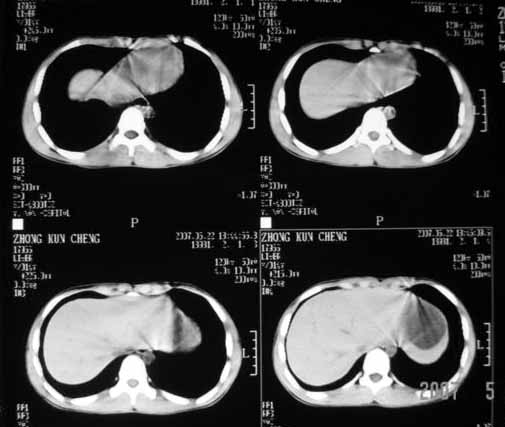

以下是引用余辉在2007-5-22 20:42:00的发言:[br]黄疸,脾脏巨大,病程短,考虑急性肝脏疾病或急性溶血性疾病,建议查肝功能及相应病毒抗体抗原

以下是引用zhangzhongshou在2007-5-22 21:04:00的发言:[br]1、脾肿大[br]2、脾脏低密度影,血管瘤?脾梗塞不能除外,建议增强扫描。

以下是引用dyqct在2007-5-22 20:45:00的发言:[br]巨脾,可疑梗塞,建议增强、查血象进一步检查

以下是引用liuyue在2007-5-23 7:57:00的发言:[br]腹主动脉周多个肿大淋巴结,脾大伴三角形低密度影,肠腔积气,考虑:1淋巴瘤2脾大伴梗塞3肠腔积气(肿大淋巴结压迫所致)